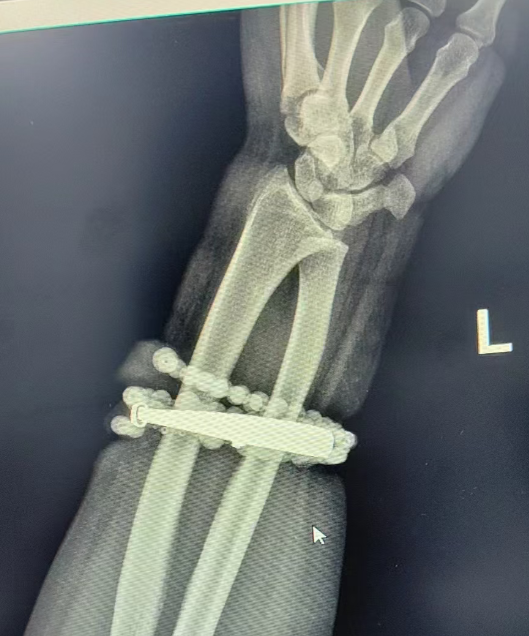

然而,就在两周前,龚女士的情况急转直下:手腕不仅疼痛加剧,还出现了明显的红肿,甚至有脓液渗出。她这才惊觉——手镯和串珠,已经有一部分“长”进了肉里,根本取不下来了!

“这是典型的首饰长期压迫、摩擦,加上细菌感染,引发的慢性炎症和肉芽组织增生。”医生介绍,此时,手镯和串珠已经成了一个不断刺激皮肤、污染伤口的“病灶”,如果不尽快手术取出,感染可能进一步扩散,甚至危及生命或影响手臂功能。

经过一个多小时的手术,医生们将手镯和串珠从厚厚的增生组织中完整剥离出来。目前,龚女士恢复良好,已顺利出院。